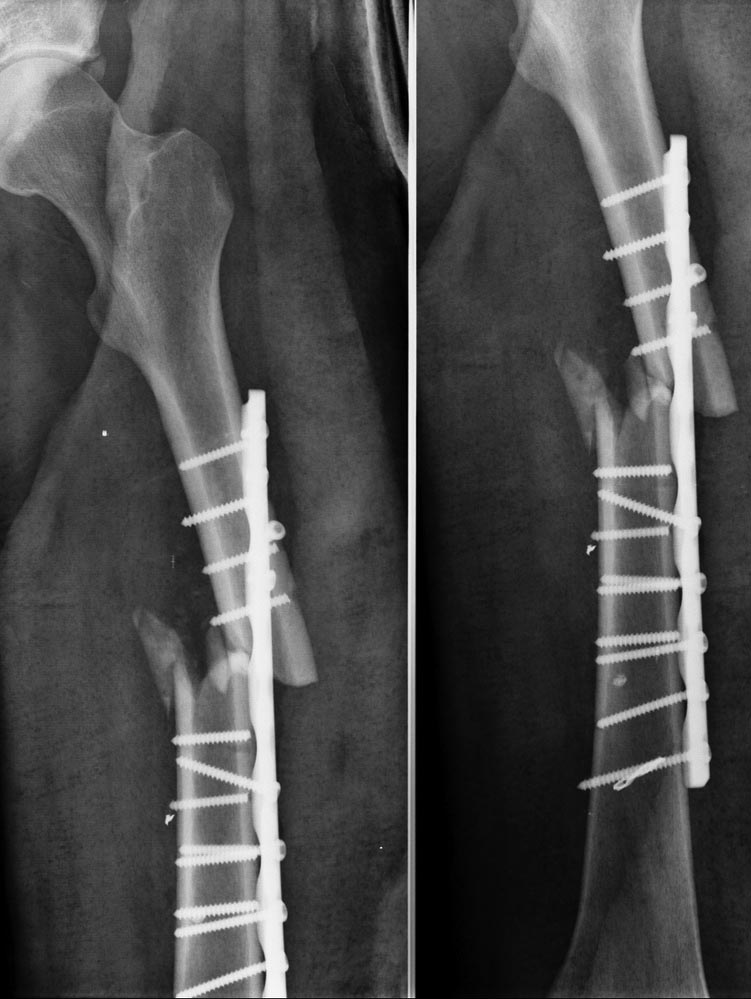

Уважаемые коллеги, к сожалению, первичных снимков у нас нет. Почему наши друзья сделали именно так, а не иначе, остается только гадать. Согласен, что выполненный МОС бедра не адекватен для типа перелома, но смущает, что перелом винтов произошел практически без нагрузки. Бывает МОС и похуже, но винты не ломаются при этом. В отделении планируется АВФ бедра, хотя рассматривается вариант и интрамедуллярного синтеза (????).

Для этого перелома пластина абсолютно не подходит, т.к. по внутренней поверхности, если я хорошо увидел имеется оскольчатый перелом, таким образом кость не "защищает" пластину, а наоборот, вызывает сильную нагрузку на варус. В таких случаях очень часто наступает дебриколяж (перелом пластины), в Вашем случае перелом винтов. Вы и сами видите, что после перелома фрагменты приняли варусное положение, сместившись в зону дефекта, фрагменты к этому стремились, они этого добились. Кроме этого пластина слишком короткая, нужно было накладывать практически на весь диафиз. Обязательно нужно было делать костную пластику по внутренней поверхности бедра в месте оскольчатого перелома и производить межфрагментарную компрессию. Но стоило ли это таких усилий? Поэтому, только ЗИМО.

задолбали со своими стержнями типа пластиной ничего делать не можно и под этот конкретный перелом пластина не подходила

Однозначно удалить пластину, винты. Рассверлить канал и относительная стабильность на штифте с блокированием. Был аналогичный случай, оперировал спустя 3 месяца, так же, коллапс импланта, варус.

Всем известно, что одной из основных причин осложнений является недостаток обеспечения на местах, потому что не везде условия как в “центре”. Перелом бедра лучше фиксировать интрамедуллярным гвоздем, но при его отсутствии пластина, как гвоздь или наружный фиксатор, может являться методом выбора. А вот рекомендации, как правильно установить пластину, были бы более полезны, чем некорректные комментарии. При открытом методе риск от гвоздя не отличается от такового при использовании пластины, и поэтому не стоит реабилитировать старый гвоздь ЦИТО. Не удаляя сломанных винтов, на пластине можно создать натуральный контур бедра, что невозможно прямым гвоздем. Стабильность конструкции создается не количеством шурупов, а правильным выбором длины пластины!